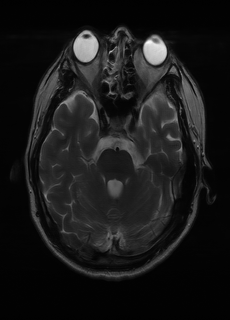

As we observe from the right image in Fig. 2, our BRM, both from MIMO and SISO settings, predicts the performance of dedicated models with a high correlation. We further choose the best three , and perform the last stage of fine-tuning accordingly to (6). A visual evaluation on real data is shown in Fig. 3. For simulated data, please refer to the Supplemental Material section.

Base on the best performing , we perceive that among , , and FLAIR, the results are best when is sampled the most. We suggest that this makes intuitive sense as images provide the best contrast out of the three sequences, which can compensate for the details lost in other images. The same observation can be made on the simulated data, where both and FLAIR show good contrast. When the time setting is changed to non-uniformity, we can see that our search for the best sampling strategy reflects the change. is sampled more as a result of faster acquisition time, while is still sufficiently sampled.

| Sequence | LR | SISO | MIMO | MIMO tuned | GT |

|---|---|---|---|---|---|

(a) 34.38/0.9371

(a) 34.38/0.9371

|

(b) 42.42/0.9883

(b) 42.42/0.9883

|

(c) 44.60/0.9920

(c) 44.60/0.9920

|

(d) 45.50/0.9940

(d) 45.50/0.9940

|

(e) PSNR/SSIM

(e) PSNR/SSIM

|

|

(f) 29.74/0.8903

(f) 29.74/0.8903

|

(g) 36.25/0.9734

(g) 36.25/0.9734

|

(h) 36.42/0.9752

(h) 36.42/0.9752

|

(i) 37.70/0.9832

(i) 37.70/0.9832

|

(j) PSNR/SSIM

(j) PSNR/SSIM

|

|

(k) 39.89/0.9311

(k) 39.89/0.9311

|

(l) 43.94/0.9864

(l) 43.94/0.9864

|

(m) 44.74/0.9883

(m) 44.74/0.9883

|

(n) 45.49/0.9894

(n) 45.49/0.9894

|

(o) PSNR/SSIM

(o) PSNR/SSIM

|